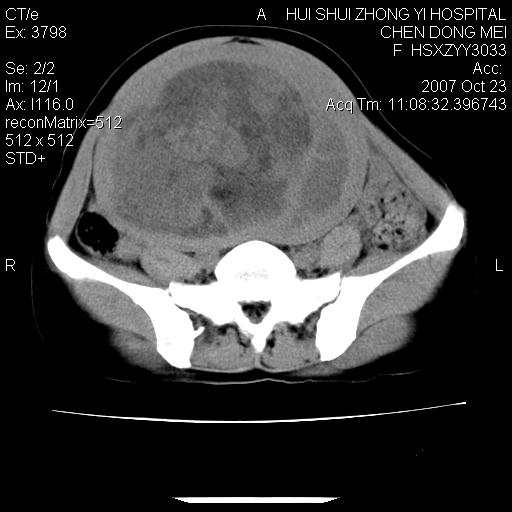

标题: CT10156:女.43岁,发现中下腹部包都块2年 [打印本页]

标题: CT10156:女.43岁,发现中下腹部包都块2年

发现中下腹部包都块2年。2年来月经不规律。

腹腔巨大软组织密度影,边缘光滑,包膜完整,内囊变坏死。腹膜后及盆腔内淋巴结肿大。结合病史考虑卵巢癌可能性大。

病变巨大,呈囊实性改变,包膜较厚且完整,内见分膈,周围脏器明显受压移位,病变与左侧附件关系密切,考虑来源左侧附件的囊腺瘤,不除外癌变可能;畸胎瘤可能性较小。

病变巨大,呈囊实性改变,包膜较厚且完整,内见分膈,周围脏器明显受压移位,病变与左侧附件关系密切,考虑来源左侧附件的囊腺瘤,盆腔内见肿大淋巴结,不除外癌变可能。

病变巨大,呈囊实性改变,包膜较厚且完整,内见分膈,周围脏器明显受压移位,病变与左侧附件关系密切,考虑来源左侧附件的囊腺瘤,不除外癌变可能